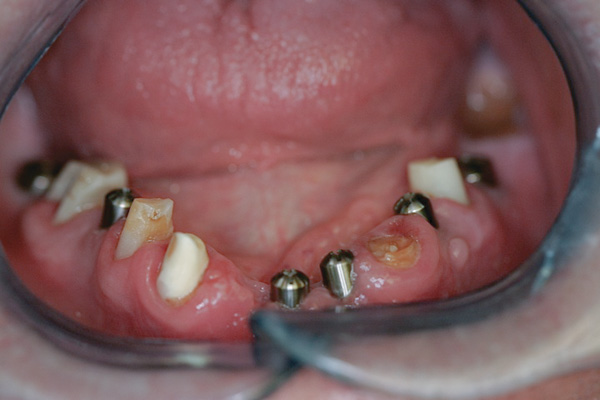

Background: This patient had a failing maxillary dentition and refused to wear a removable prosthesis. A staged approach was employed to retain some of his natural tooth abutments, and recession was noticed at the time of the impression for the second group of implants. Figure 1 shows the patient following insertion of the first set of implant custom abutments; the adjacent natural teeth are still present to support the provisional bridge. Seven months later, as shown in Figure 2, those first-stage custom abutments exhibited evidence of 1 mm to 3 mm of recession.

Figure 1  Patient following insertion of first set of implant custom abutments.

Figure 1